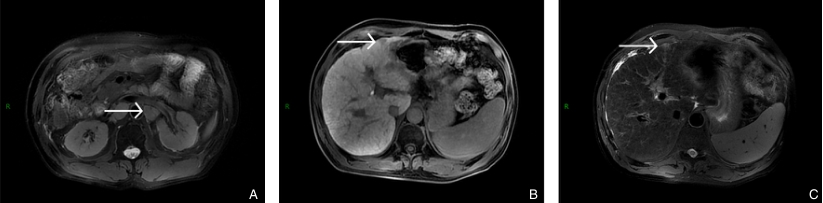

图4 患者转化治疗后MRI A-B:病变在T1加权成像(T1WI)中呈稍低信号,在T2加权成像(T2WI)中呈高信号;C:原肿大淋巴结消失Fig.4

图6 2023年6月与2024年9月患者术后复查MRI A:复查可见复发淋巴结;B-C:复查病变在T1加权成像(T1WI)中呈稍低信号,在T2加权成像(T2WI)中呈高信号Fig.6